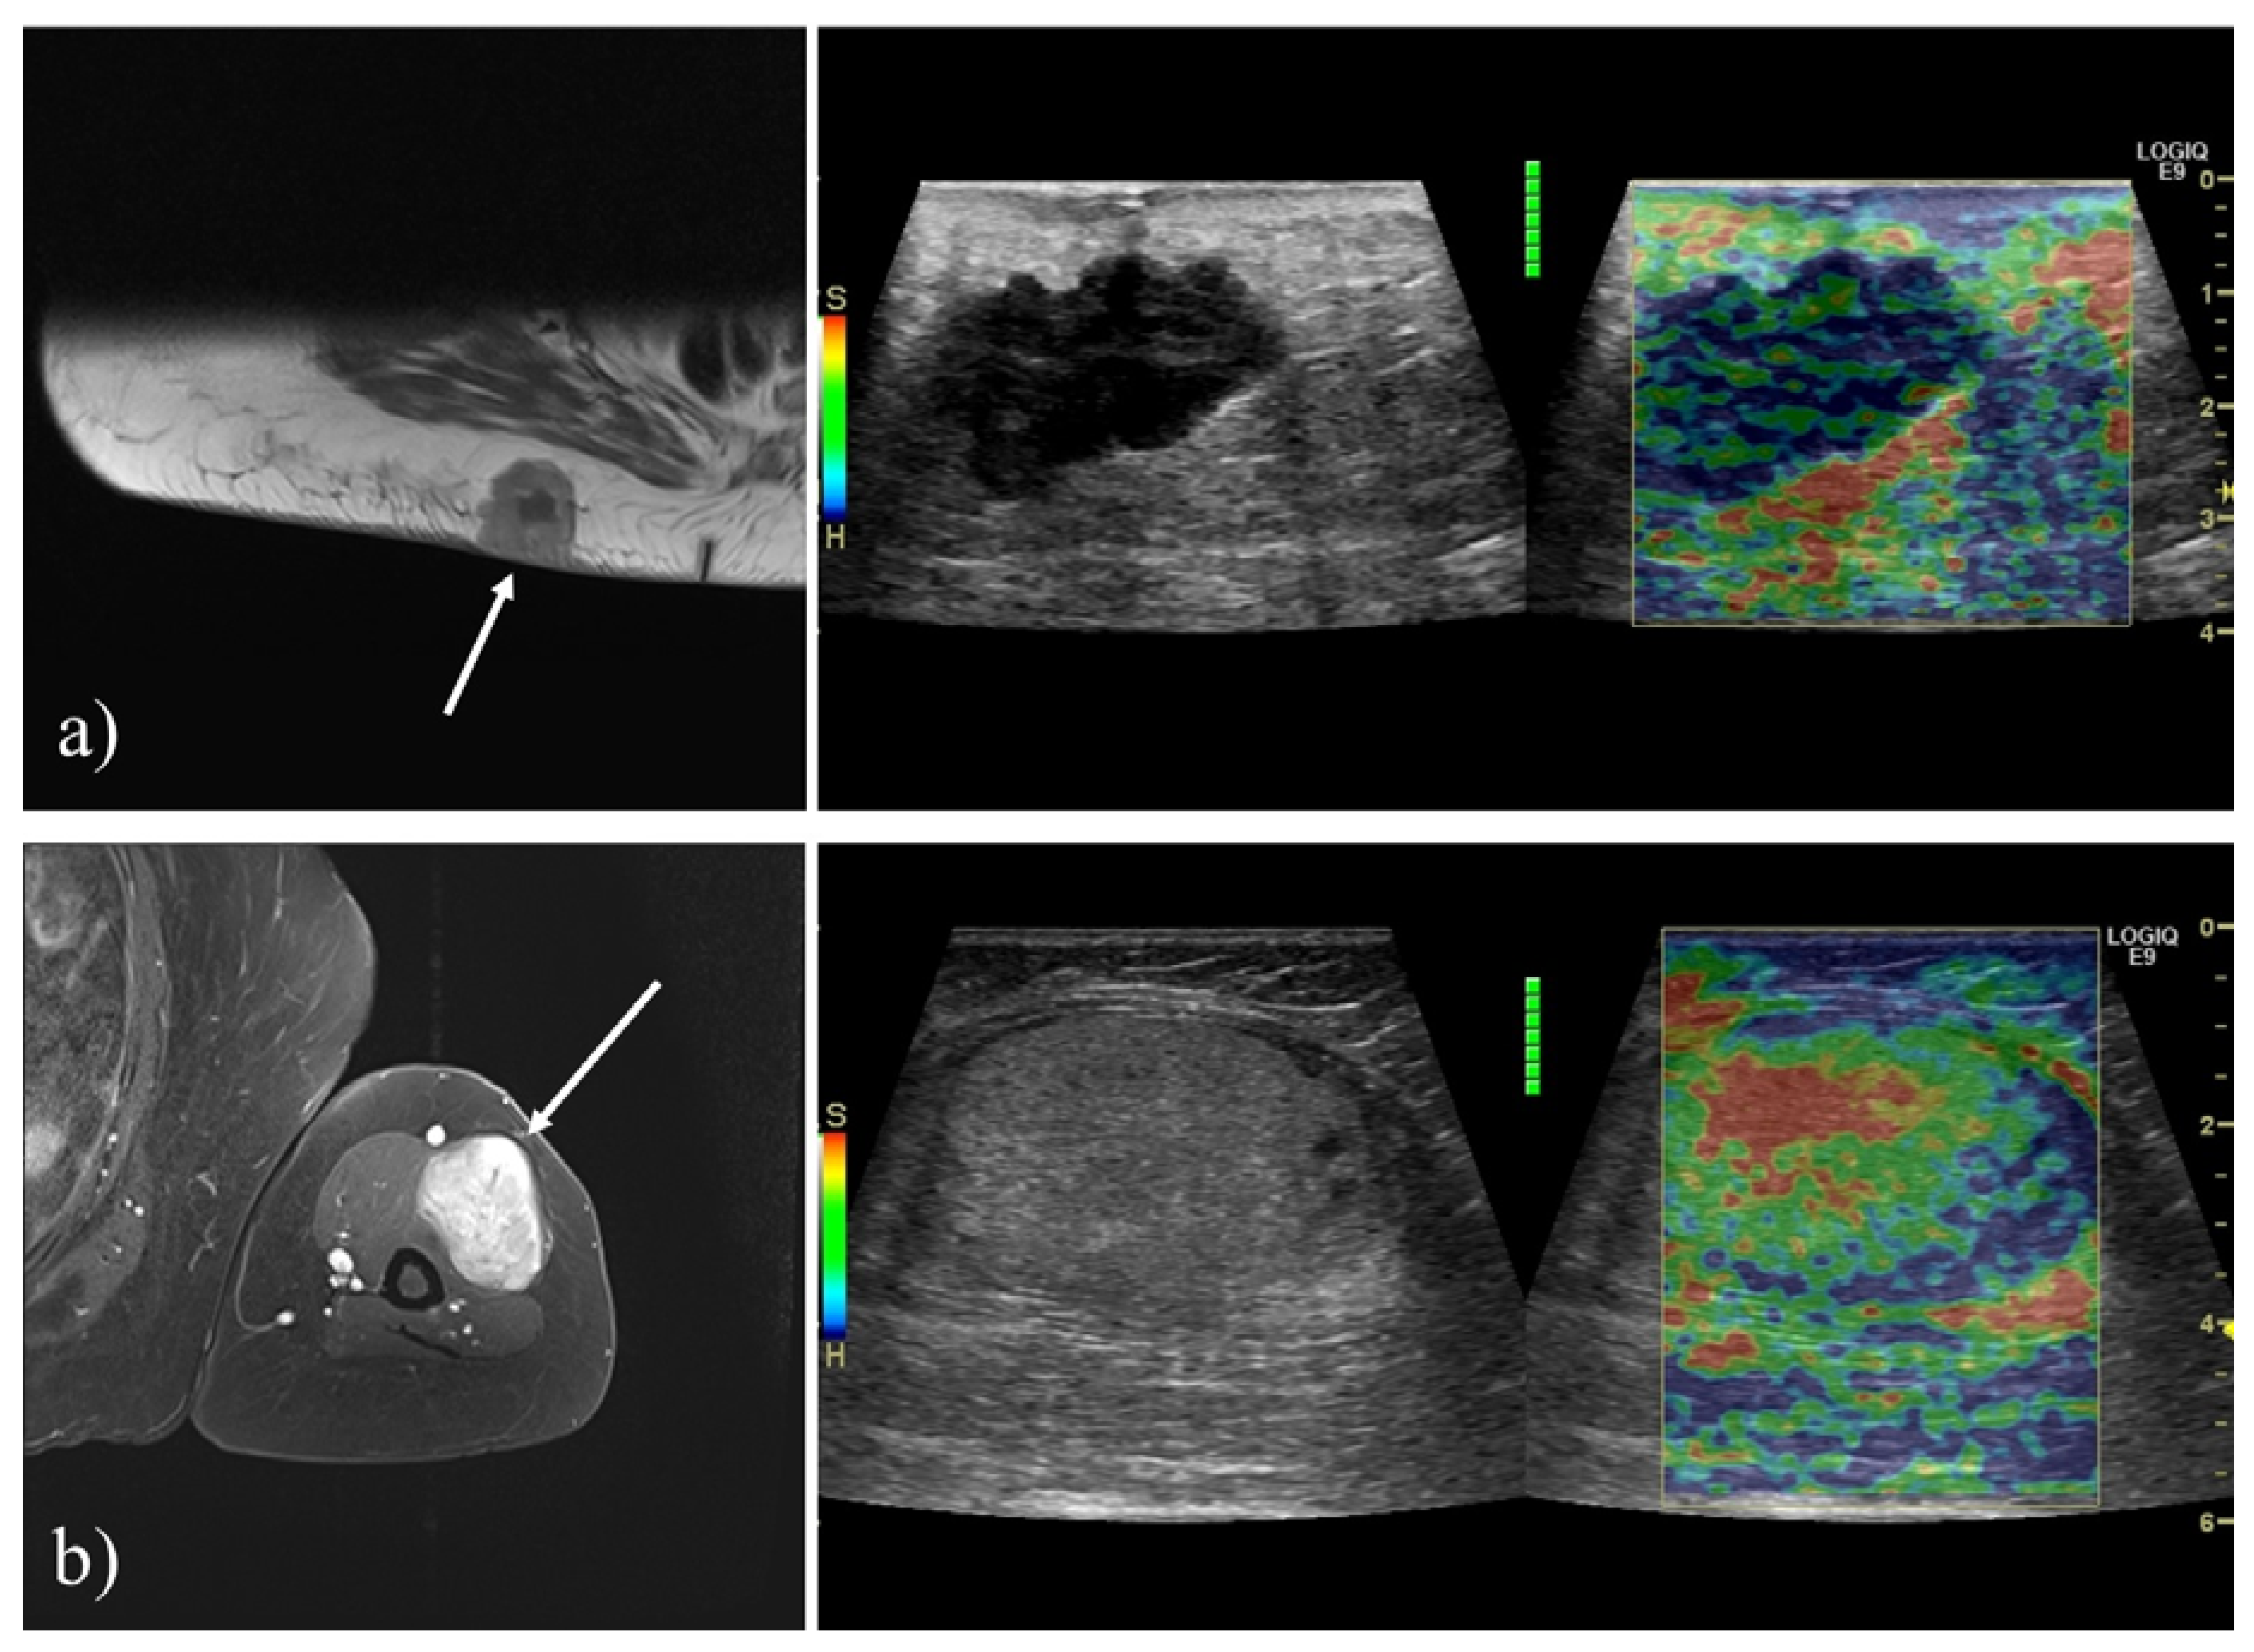

All elastography examinations were performed by one of five different physicians, who all had extensive experience with the technique. Gentle compression was applied using the US transducer, at a frequency of 1.3–2 Hz, with continuous monitoring of elastogram quality using the quality indicator provided by the US system. Multiple 10-s elastography cine loops were stored. The color scale was adjusted to show stiff tissue as blue and soft tissue as red (Figure 2).

Figure 2. Examples of tumors included. (a) A 71-year-old female with metastasis of malignant melanoma. T1-weighted transverse contrast-enhanced MRI showing a lesion superficial to the right gluteal musculature. The tumor appeared hypoechoic and irregular on B-mode US, and SE revealed the tumor to be hard (blue). (b) A 75- year-old female with a chondroid lipoma. T1-weighted fat suppressed contrast enhanced MRI showing a tumor in the anterolateral upper arm. B-mode US and strain elastography (SE) revealed the tumor to be isoechoic, homogenous and soft (red).